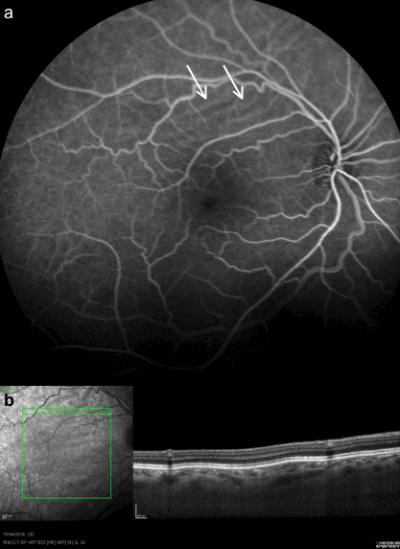

The left retina was normal. A fundus fluorescein angiogram (FFA) showed the characteristic alternating black and white striae (Figure 2a). The optical coherence tomography (OCT) scan showed undulations in all the layers of the retina (Figure 2b). A MRI scan of the orbit and thyroid function tests were reported as normal.

Figure 2a: Fundus fluorescein angiogram showing characteristic alternating black and white striae.

Figure 2b: OCT scan showing undulations in all the layers of the retina.